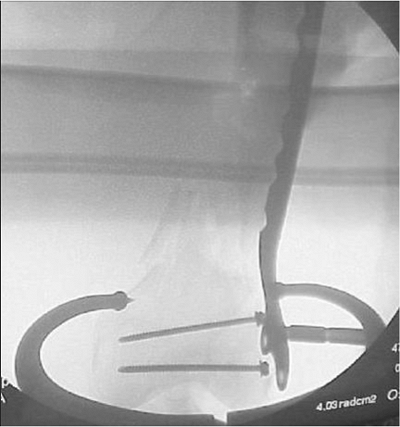

the guide pin for the screw is drilled into the lateral condyle such

that it is parallel with the trochlear notch in the axial plane (Fig. 45.7)

and parallel with the distal tips of the femoral condyles in the AP

plane. This guide wire is 2 cm proximal to the distal ends of the

condyles and slightly anterior to the midline on the lateral view (Fig. 45.8).

The guide pin is overdrilled with the cannulated reamer and the screw

is inserted. To keep the side plate aligned with the lateral cortex, a

Kirschner (K) wire is placed into a screw hole proximally during the

early part of this process. The side plate is

attached

and the shaft screws are inserted distal to the fracture site. An

allograft strut is applied to the anterior cortex with minimal

stripping and held in place with cerclage wires rather than cables.

Proximal to the fracture site, these cables will also hold the end of

the side plate onto the bone (Fig. 45.9).